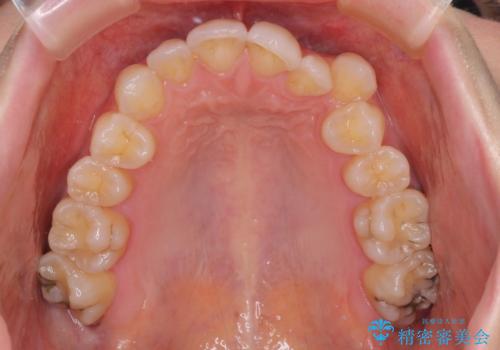

- 八重歯や前歯のデコボコを気にして来院された患者様です。

骨格的な左右差と、歯列から外れている歯が上下で左右非対称になっていることから、上下正中が歯1本分ずれている状態でした。

八重歯の改善と、上下の正中位置を極力合わせていくことを目的として、上下左右の第一小臼歯4本を抜歯し、ワイヤー装置にて矯正治療を行うこととしました。